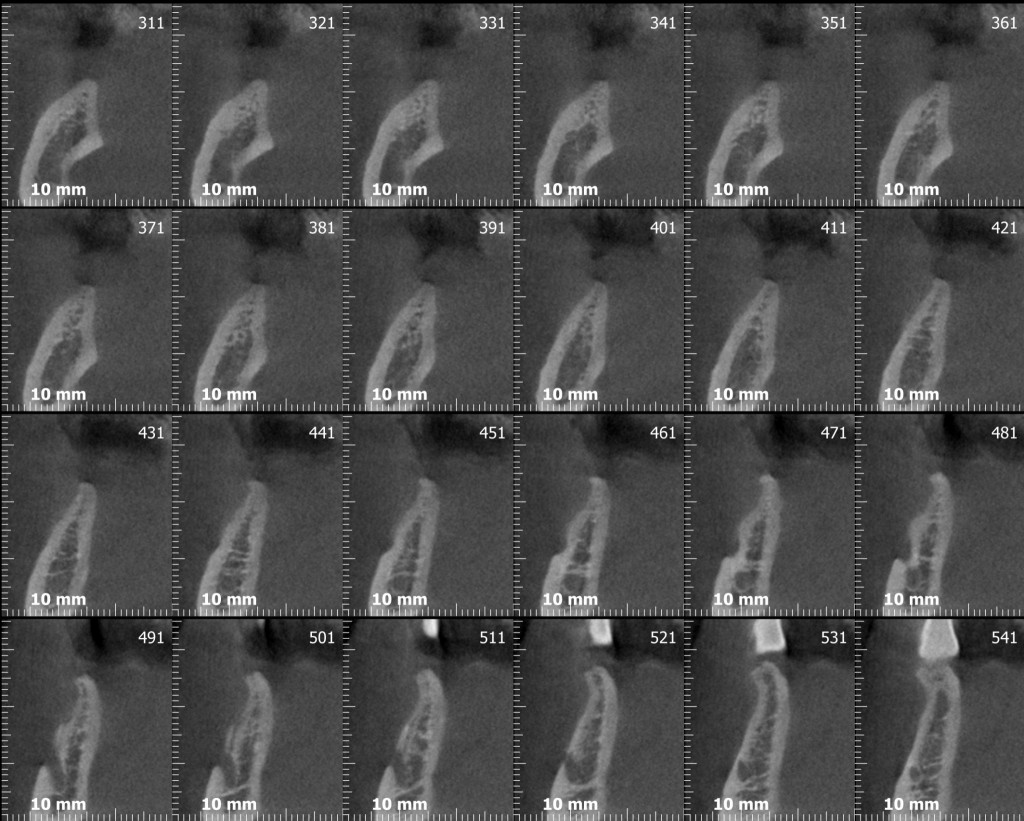

Il signor Franco, nostro paziente da quasi dieci anni, qualche mese fa ha finalmente deciso di mettere gli impianti che gli avevamo proposto nel lontano 2007. Già dalla foto dovresti notare una marcata atrofia verticale e orizzontale. Come mio solito faccio fare una radiografia tridimensionale per progettare l’intervento in sicurezza e spiegare al paziente esattamente cosa andrò a fare durante la seduta chirurgica…

Cosa vedi? Ok, una bella atrofia orizzontale, associata ad una modesta atrofia verticale. Come possiamo trattare una atrofia verticale associata ad una orizzontale? (rimanendo all’interno dell’evidence based medicine per carità!)

Te lo dico io: GBR (con vari tipi di barriere) o innesti a blocco. Io utilizzo entrambe le tecniche ma in questo caso, per una serie di motivi che forse un giorno discuteremo, ho optato per l’innesto a blocco.

Avevi notato questo? Dai tagli della cone-beam si nota chiaramente una variante anatomica abbastanza importante: un foro mentoniero accessorio posizionato più o meno a metà tra la cresta e il foro primario, diciamo circa 7 mm apicalmente alla cresta, dal quale emerge un ramo di diametro rilevante del nervo alveolare inferiore. Chissà a quale parte del mento o del labbro porta le sensibilità quel piccolo ramo!? Diciamo che per mantenere immacolato il mio palmares medico legale preferisco non scoprirlo!